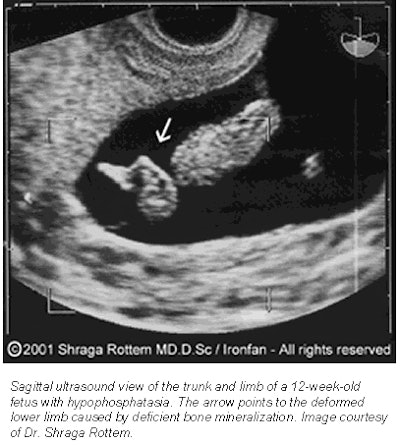

![]() |